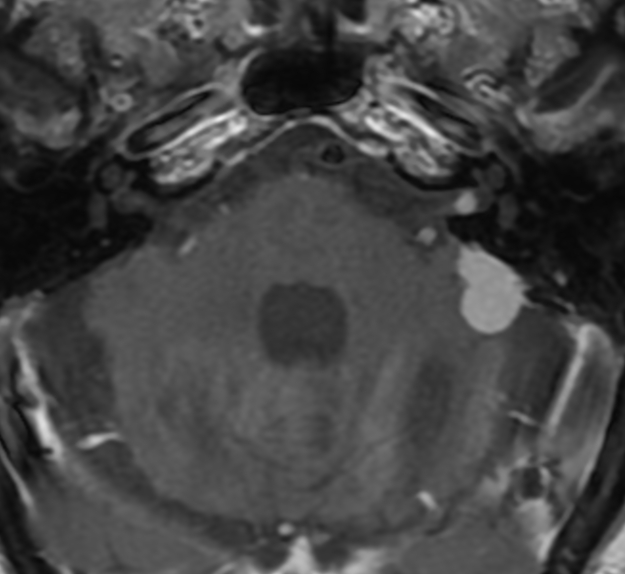

Gul Moonis@gmoonis·

When one image suffices for the two commonest lesions of the IAC/CPA, vestibular schwannoma and meningioma on the same side #radres #hnrad @columbiaimaging

Gul Moonis tweet media